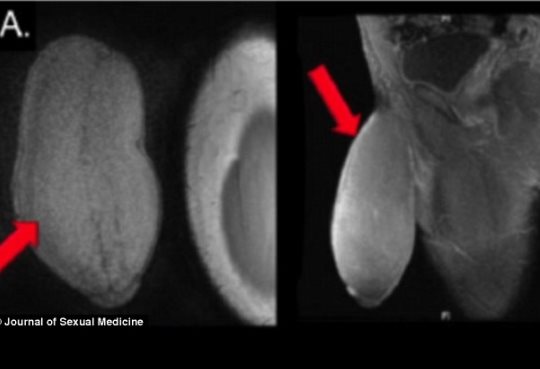

Σε επέμβαση συρρίκνωσης πέους υπεβλήθη ένας Αμερικανός 17χρονος έφηβος επειδή το γεννητικό του όργανο ήταν υπερβολικά μεγάλο και τον εμπόδιζε να κάνει σεξ και να συμμετέχει σε ορισμένα αθλήματα.

Το πέος του έφηβου είχε διάμετρο 25 εκατοστά και μήκος 17 εκατοστά. Οι χειρουργοί του περιγράφουν το σχήμα του σαν μια μπάλα αμερικανικού fotball.